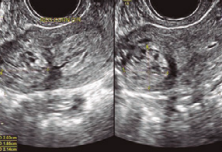

Gestante de 36 anos, primigesta e sem antecedentes mórbidos, obstétricos ou ginecológicos relevantes, realizou a primeira coleta de ßHCG com 6 semanas e 2 dias (1.498 UI/L). Em seguida, fez coletas repetidas de ßHCG, assim como a ultrassonografia transvaginal, como detalhado no quadro 1. Com 7 semanas e 6 dias, apresentou sangramento vaginal moderado e intermitente e, assim, uma nova coleta de ßHCG foi realizada com 8 semanas (5.440 UI/L). A ultrassonografia transvaginal, feita com 8 semanas e 1 dia, levantou a suspeita de gestação ectópica cornual (imagem 1). A repetição desse exame após uma semana evidenciou aumento da imagem heterogênea em região cornual uterina à direita (imagem 2).

IMAGEM 1- Ultrassonografia transvaginal, 8 semanas e 1 dia, mostra imagem heterogênea em região cornual direita

IMAGEM 2- Ultrassonografia transvaginal, 9 semanas e 1 dia, aponta imagem heterogênea em região cornual direita.